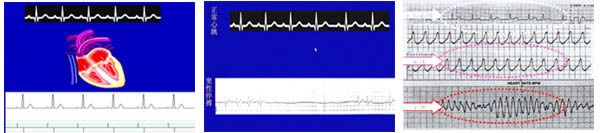

主持人:哪些原因可以引发晕厥? 华伟:晕厥可以分为心源性晕厥和非心源性晕厥两大类,心源性晕厥也就是心血管疾病引起的晕厥,后果比较严重甚至会造成死亡。非心源性晕厥包括血管迷走性晕厥和神经性疾病,这种晕厥临床比较多见,但是严重程度远远比不上心源性晕厥。 张澍:一般说来有心脏病的人都有可能产生晕厥,但并不是说心脏病患者就一定会产生晕厥,能够表现晕厥的心脏病包括两种情况1、有严重的心律失常。2、心脏排血受阻,包括梗阻性心肌病、主动脉瓣严重狭窄等。 华伟:来看一张片子,正常的心跳是很规则的,心跳过快或过慢都会引起心脏排血量不足,从而引起脑缺血引发晕厥。

主持人:山东田女士 我父亲平时心跳较慢,有一天饭后散步时突然晕倒,全身抽动,过了好几分钟又醒过来了,这是怎么回事,需要治疗吗? 华伟:患者是由于心脏停跳较长引起脑缺血导致晕厥。针对这种情况最有效的治疗方法就是运用心脏起搏器,来看两张图,心脏起搏器可以帮助心脏跳动维持窦性心律,将起搏器埋入胸部的囊袋中,将导线放至心脏处,患者需要终身戴起搏器,起搏器的寿命是8年左右,需要定期更换。

主持人:天津周先生 我老伴去年发生过心肌梗塞,一个月前突然晕倒,几分钟后才醒过来,前几天又出现过同样的情况,现在家里人都很紧张,请问该怎么办? 张澍:这是一位冠心病患者,在急性冠状动脉缺血的情况下会导致严重的心律失常,由于短时间内心脏排血受到限制发生了晕厥。这种晕厥是很严重的,处理得不好甚至会导致猝死。患者一旦确定是这种原因的晕厥,可以采用心律除颤转复器进行治疗。如图,这种除颤器同火柴盒的大小相仿,可以埋在体内,当患者发生室性心动过速或室颤时,除颤器可以自动识别并放电,及时除颤挽救患者的生命。